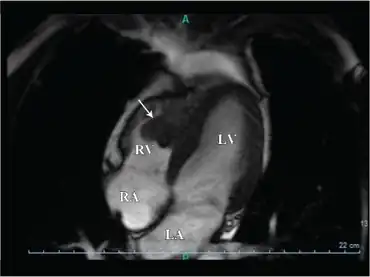

The excessive clotting that occurs in this disorder is almost always restricted to the veins,[13] where the clotting may cause a deep vein thrombosis (DVT). If the venous clots break off, these clots can travel through the right side of the heart to the lung where they block a pulmonary blood vessel and cause a pulmonary embolism. It is extremely rare for this disorder to cause the formation of clots in arteries that can lead to stroke or heart attack, though a "mini-stroke", known as a transient ischemic attack, is more common. Given that this disease displays incomplete dominance, those who are homozygous for the mutated allele are at a heightened risk for the events detailed above versus those who are heterozygous for the mutation.[14]